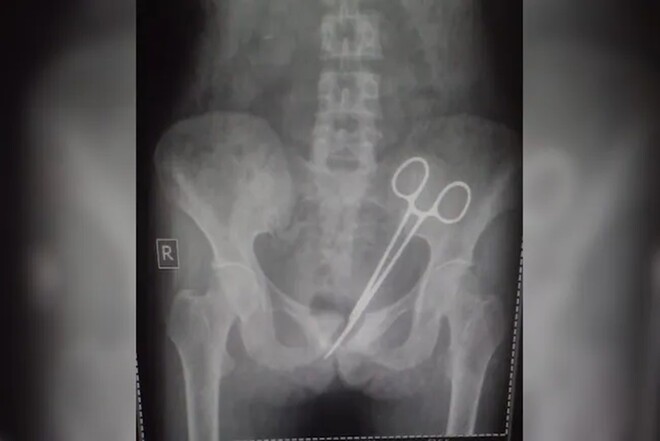

8 اکتوبر کو خاتون دوبارہ ہسپتال گئیں اور ایکسرے سے پتہ چلا کہ ان کے پیٹ میں قینچی ہے (فوٹو: این ڈی ٹی وی)

8 اکتوبر کو وہ دوبارہ اسی ہسپتال گئیں اور ایکسرے سے پتہ چلا کہ ان کے پیٹ میں قینچی ہے۔